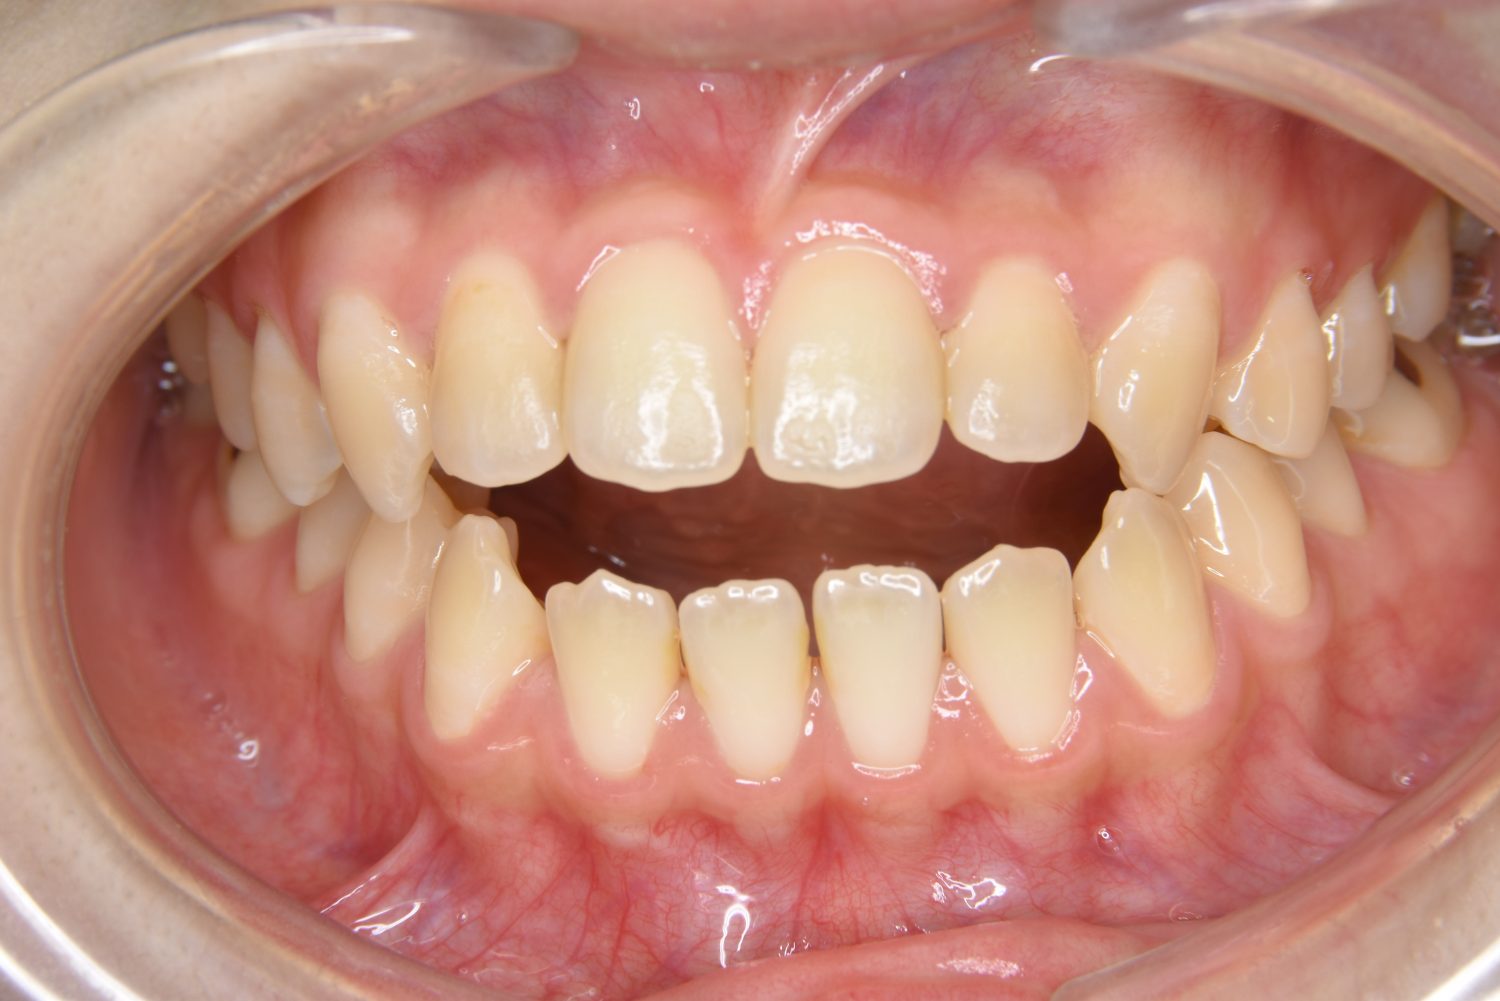

前歯部開咬の症例紹介①

Before

主訴

前歯が開いているのが気になる。

治療内容

上リンガルブラケット(舌側装置)、下ラビアルブラケット(唇側装置)に矯正用アンカースクリューを併用し非抜歯で治療を行いました。

上下の前歯が開いており前歯では全く噛めていない状態でした。臼歯の圧下を行うことで前歯でも咬合できるようになり機能面のみでなく審美面も著しく改善しました。